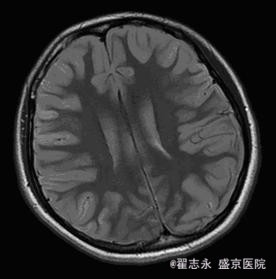

查体:昏迷,瞳孔等大,直径3.5mm,光反射迟钝。四肢疼痛刺激可见收缩反应。余查体不能配合完成。 头MRI的Flair及DWI如图。

诊断:缺血缺氧性脑病

新生儿缺血缺氧性脑病的早期表现有广泛脑水肿、颅内出血、皮质下及脑室旁白质损害、丘脑及基底节区和脑干背侧异常信号等; 晚期可表现为脑室周围脑白质软化症、分水岭区脑损伤等。而成人早期( 10 d 内) MRI 可表现为脑水肿、灰白质分界消失、大脑皮质层层状坏死、颅内出血; 晚期( 10 d~6 个月) 可表现为皮层下白质及深部白质脱髓鞘改变、选择性神经元坏死、广泛脑损害、脑萎缩。